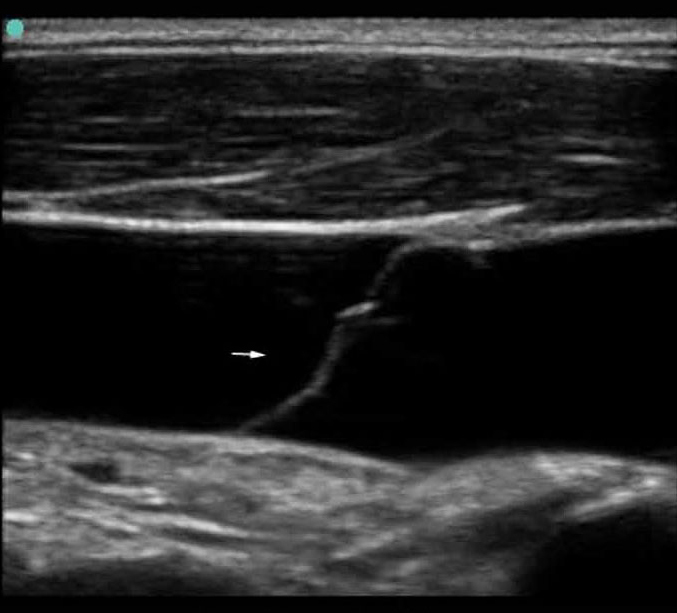

S Series: IJV Long Axis Valve Closed